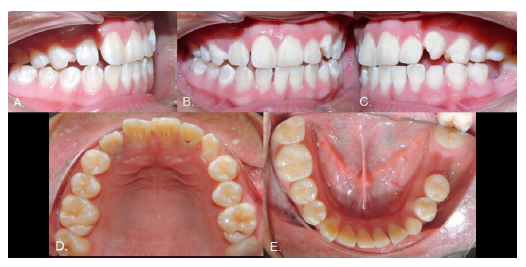

Case 7

Female, 16 years of age. The 1.5, 2.1, 3.5, 4.3, and 4.5 teeth were missing, and the inferior right primary canine and two primary second molars were still present (Fig. 13). The radiograph showed that the 4.3 was in type 1 transmigration, the 1.5, 3.5, and 4.5 exhibited agenesis, and the 2.1 was impacted and had an associated supernumerary tooth (Fig. 14A). The simultaneous presence of supernumeraries and agenesis is a very rare (0.33%) condition known as concomitant hypo-hyperdontia (14). As in Case 6, the 4.3 was near the roots of neighboring teeth and the CBCT revealed a lesion that extended from the right deciduous canine to the left lateral incisor, almost as if showing the path that the transmigrated canine had followed (Fig. 14, B-D), so it was extracted. The 2.1 was surgically exposed and a post attached to it to allow its movement with orthodontics. The gap for the 1.5 was to be closed using orthodontics, but the spaces for the inferior premolars were to be maintained for later rehabilitation with dental implants (Fig. 15).